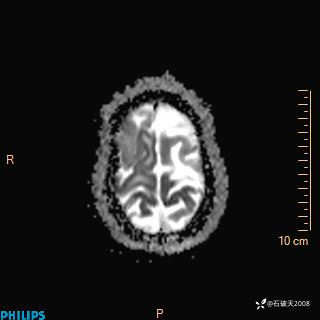

2020.11.14MR

DWI

ADC